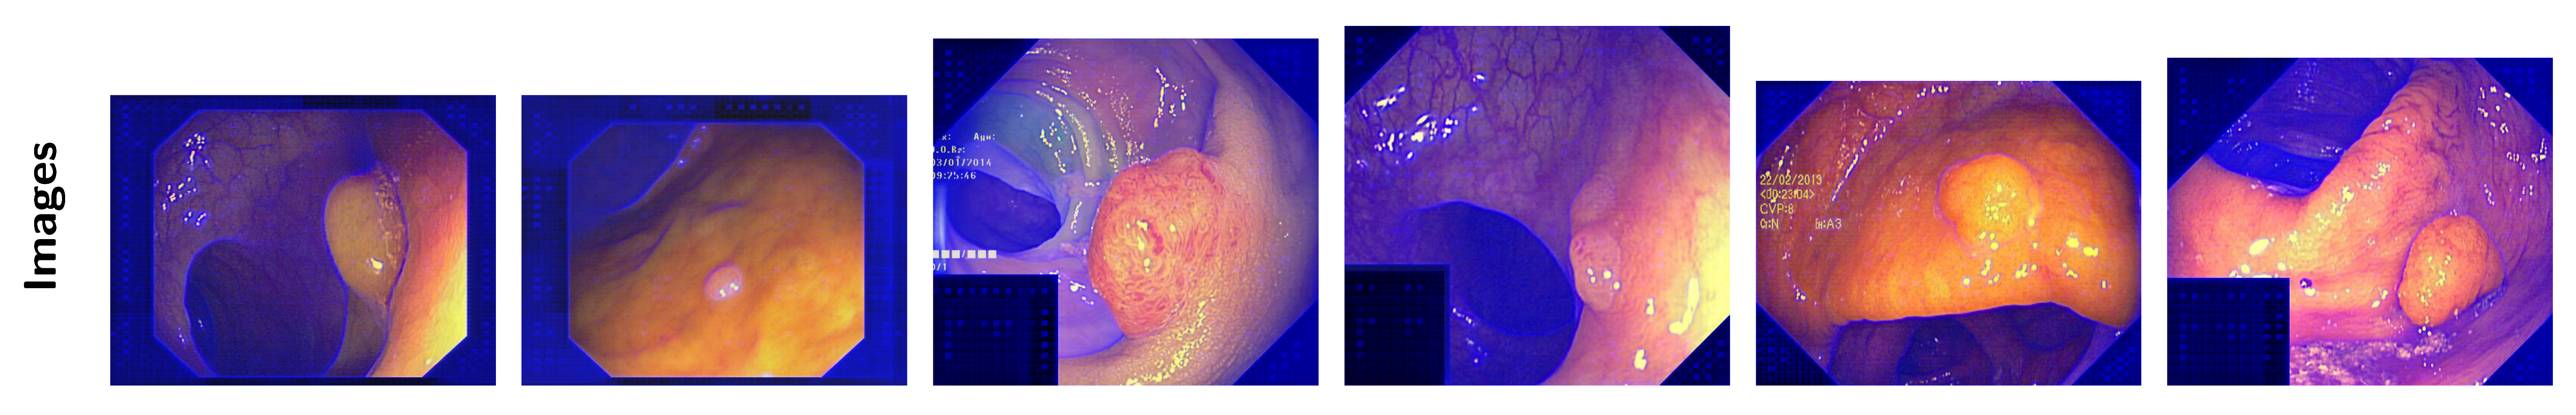

2.5.1. Polyp Segmentation

- CVC-T [34] contains 300 images. It is a test set derived from the larger CVC-EndoSceneStill dataset, which includes colonoscopy images with different polyp presentations.

- CVC-ClinicDB [35] (ClinDB) includes 612 images extracted from 31 videos of colonoscopy procedures. Expert annotations identify polyp regions, and ground-truth data are also available for light reflections. The images in this dataset are uniformly sized at 576 × 768 pixels.

- Kvasir-SEG [36] (Kvasir) contains 1000 images meticulously labeled and verified by medical professionals. This dataset features various segments of the digestive system, including both healthy and diseased tissue. The images have resolutions ranging from 720 × 576 pixels to 1920 × 1072 pixels and are organized into folders based on content. Some images also include a small picture-in-picture display indicating the position of the endoscope within the body.

- CVC-ColonDB [37] (ColDB) contains 380 images and provides a diverse range of polyp appearances to maximize dataset variability and encompass various polyp types and scenarios.

- ETIS-LaribPolypDB [38] (ETIS) consists of 196 colonoscopy images, which are valuable for evaluating segmentation performance due to their variety and quality.

- PolypGen [39] is an open-access resource containing 1537 polyp images. It was collected from six centers across Europe and Africa, offering a total of 3762 positive frames and 4275 negative frames. These images represent diverse populations, endoscopic systems, and surveillance expertise from Norway, France, the United Kingdom, Egypt, and Italy.